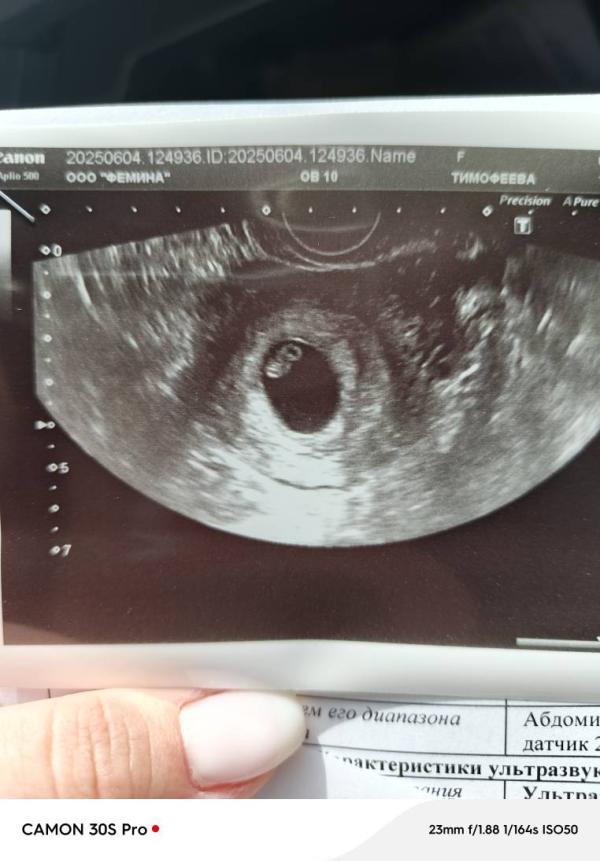

Второе узи. Такой уже человечек прям 😍